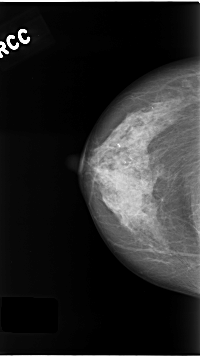

C_0180_1.RIGHT_CC

RIGHT_CC LINES 4680 PIXELS_PER_LINE 2600 BITS_PER_PIXEL 12 RESOLUTION 50 NON_OVERLAY

RIGHT_MLO LINES 4688 PIXELS_PER_LINE 2520 BITS_PER_PIXEL 12 RESOLUTION 50 NON_OVERLAY